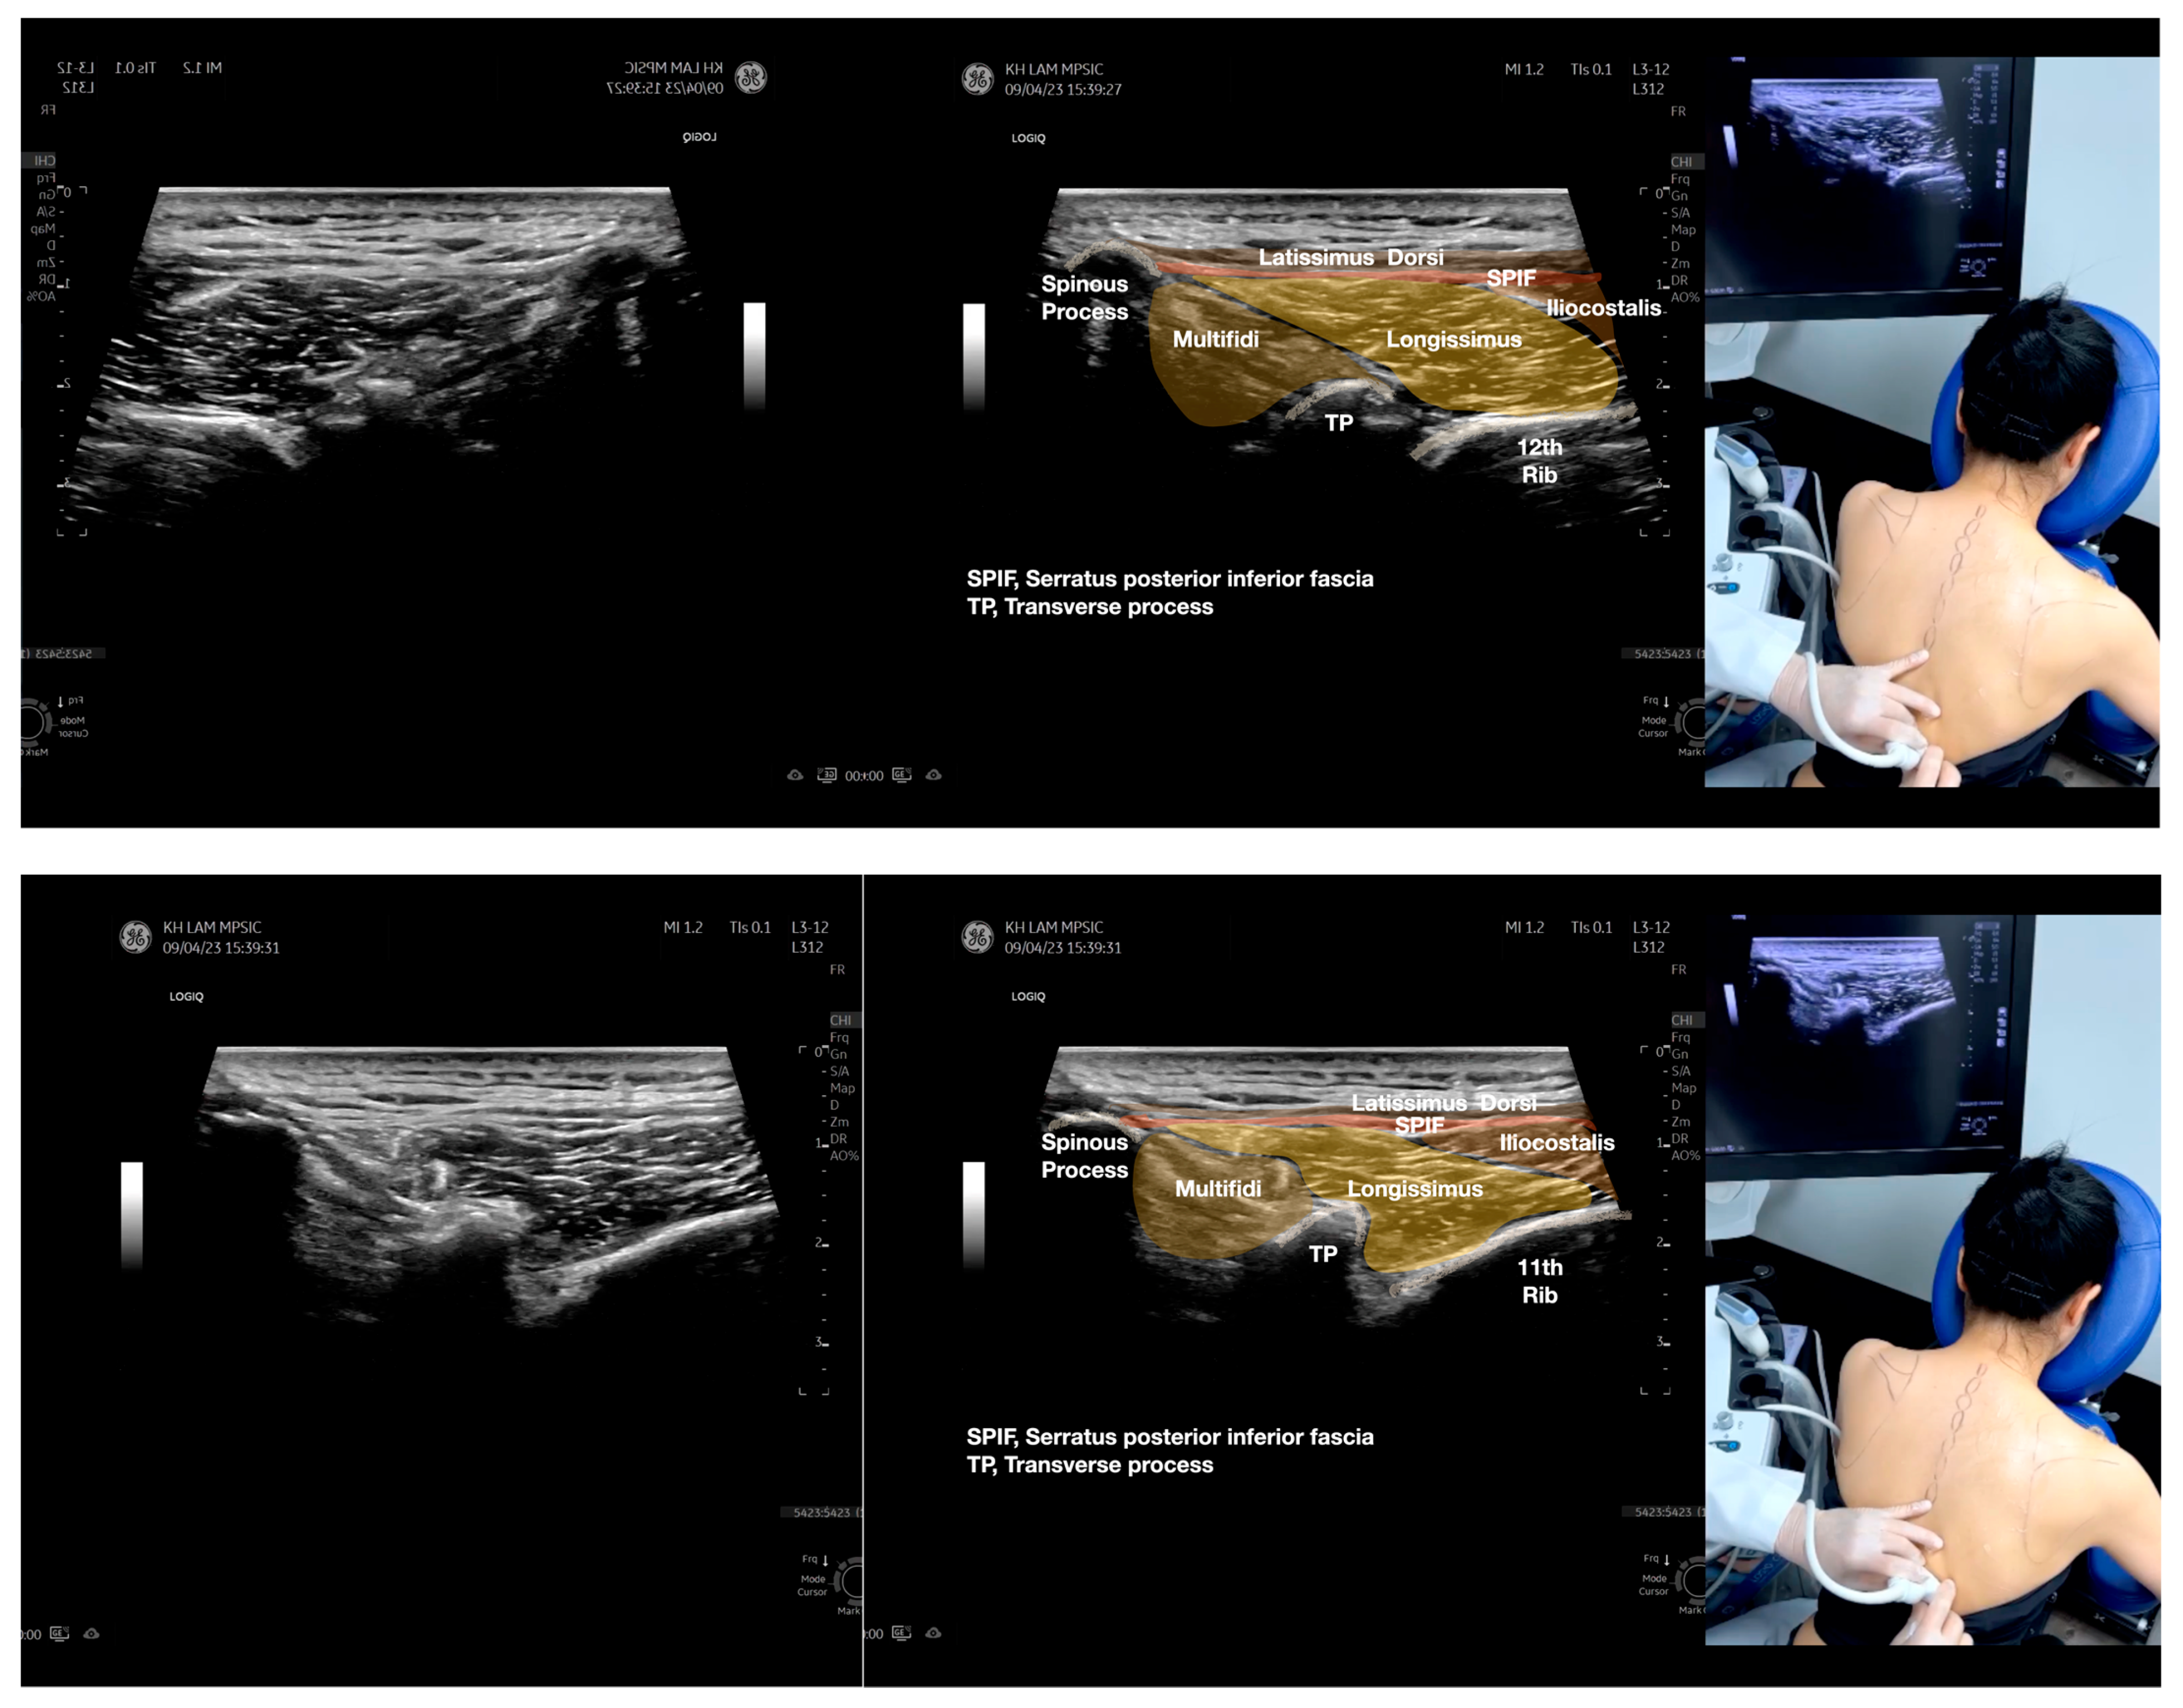

Figure 4.

Sonoanatomy of the medial edge of the scapula, its related muscles, and the infraspinatus fascia. The step-by-step scanning techniques of these structures illustrated in this figure have been shown in Video S8. Available online: https://www.dropbox.com/s/iaej3rxhl83kqt4/Figure%204.docx?dl=0 (accessed on 1 January 2023).